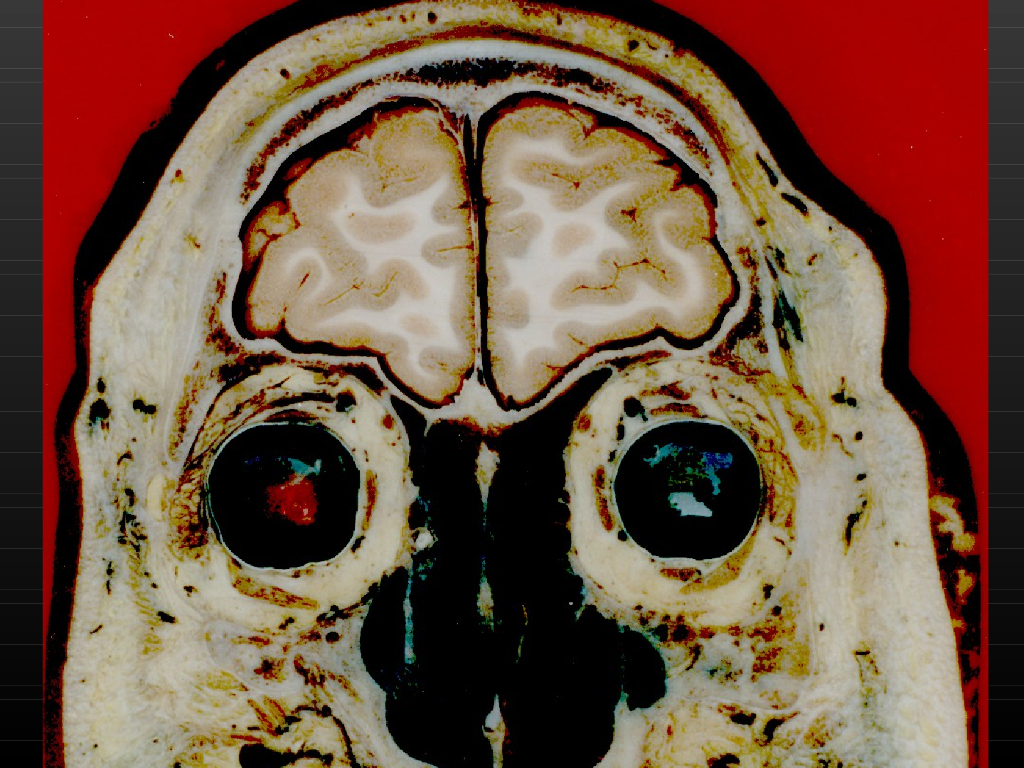

《断层影像解剖学》演示文稿-头部冠状断层解剖与MRI.pdf